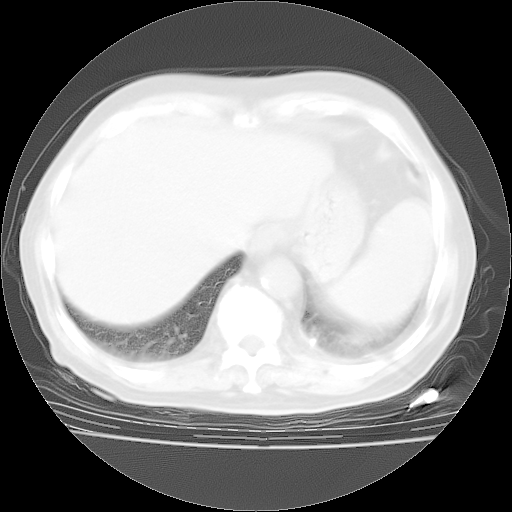

4月28日肺部CT——再次出现类似去年5月9日——磨玻璃样、间有“粟粒样”改变。